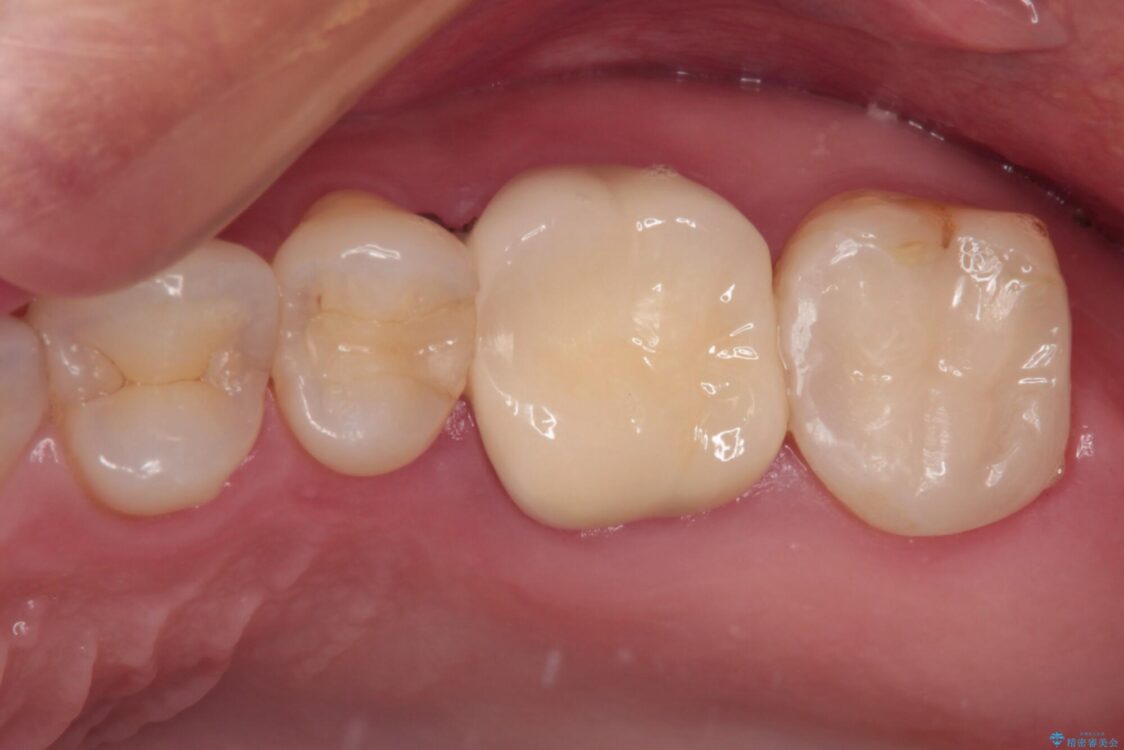

強い咬合力を負担する第一大臼歯であるため、根管治療後は速やかにオールセラミッククラウンにて補綴治療を行うこととしました。

初診時は神経組織の生活反応が認められましたが、2日後に処置を行ったときには、既に反応はなくなっている状態でした。

神経組織は壊死が始まっておりましたが、初回処置後には痛みを感じることもなくなり、2回目に無事に根管治療を終えることができました。

治療後

• 奥歯がズキズキと痛む 奥歯の虫歯治療 治療後画像